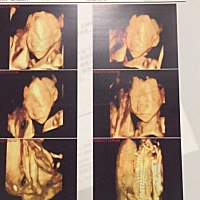

四维顺利通过,大家帮忙看看男孩女孩、娱乐一下